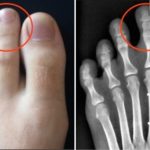

Η φλεγμονή είναι η πρώτη αιτία χρόνιων ασθενειών, όπως είναι η αρθρίτιδα η ουρική αρθρίτιδα και η οστεοαρθρίτιδα. Ευτυχώς, ο μαϊντανός μπορεί να βοηθήσει αρκετά στην αντιμετώπισή τους.